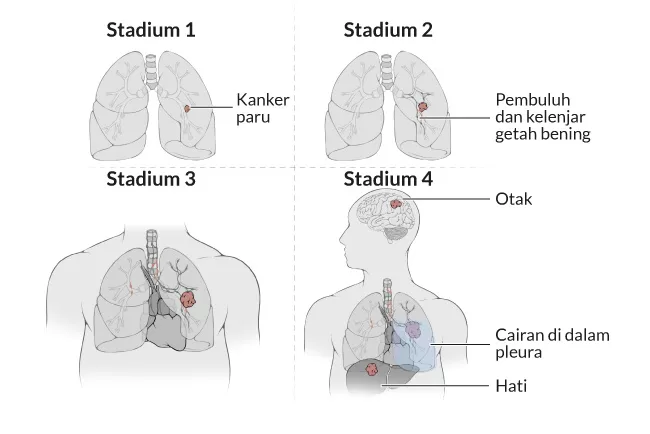

10. Kanker Paru-Paru

Kanker paru-paru adalah kelainan karena pertumbuhan sel kanker yang tidak terkendali di dalam jaringan paru-paru. Kanker ini mempengaruhi pertukaran gas di paru-paru dan menjalar ke seluruh bagian tubuh. Merokok merupakan penyebab utama dari sekitar 90% kasus kanker paru-paru pada pria dan sekitar 70% kasus pada wanita.

Semakin banyak rokok yang dihisap, semakin besar risiko untuk menderita kanker paru-paru. Namun tidak menutup kemungkinan perokok pasif pun mengalami penyakit ini Penyebab lain yang memicu kanker paru-paru adalah penderita menghirup debu asbes, kromium, produk petroleum, dan radiasi ionisasi.